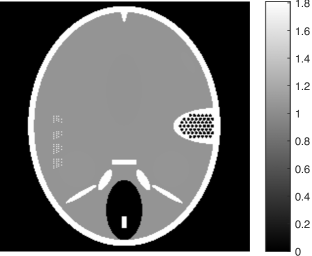

Figure 2. Results of different methods for reconstructing the head phantom with underdetermined rate 25% and relative noise level 0.2. (a) FBP (SNR=0.3253), (b) Landweber (SNR=0.1718), (c) Kaczmarz (SNR=0.1406), (d) L2-TV with scalar λ𝜆\lambda (SNR=0.0644), (e) Our method (SNR=0.0525), (f) λ𝜆\lambda in our method.

Figure 3. Results of different methods for reconstructing the head phantom with underdetermined rate 25% and relative noise level 0.8. (a) FBP (SNR=0.3505), (b) Landweber (SNR=0.1740), (c) Kaczmarz (SNR=0.1448), (d) L2-TV with scalar λ𝜆\lambda (SNR=0.1072), (e) Our method (SNR=0.0762), (f) λ𝜆\lambda in our method.

In Figure 2 and 3, we give the reconstruction results, which are shown in the same intensity range as the original phantom, from the simulated measurements with the noise level 0.2 and 0.8, respectively. Since the FBP algorithm is according to the analytical formulation of the inverse X-ray transform, it implicitly requires to have continuously measured clean data from the whole 0 to π𝜋\pi angular range. Therefore, it is not suited for reconstructing from noisy limited data. We can clearly see many stripe artifacts due to the noise and sparse projection angles in the FBP results. Both the Landweber and Kaczmarz’s methods perform better than FBP, but there are still some visible artifacts in the reconstruction. By using the TV regularization in the L2-TV and our methods, we potentially assume that the reconstructions are piecewise constant, which evidently reduces the influence of the noise and avoids stripe artifacts. In addition, comparing the results from the L2-TV and our methods, we find that our method suppresses artifacts much better while reconstructing most details. For instance, the grey region in the head and the black dotted region on the right side. With respect to SNR, it is also clear that our method gives the best reconstruction results. In Figure 2 (f) and Figure 3(f), we also plot the λ𝜆\lambda function obtained by our method. One can see that in the more textured regions λ𝜆\lambda is large in order to preserve the details, and in the more homogenous regions it is small to reduce artifacts.